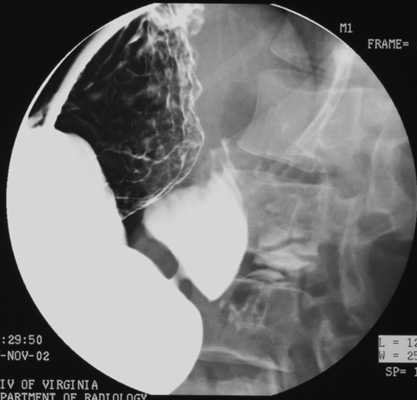

Following the DC examination of the esophagus and stomach, perform

single-contrast graded-compression (SCGC) spots. Turn patient into

right anterior oblique (RAO) position. Place compression paddle beneath

patient and inflate balloon for graded compression of duodenal bulb. Take

one SCGC spot (Zoom to 6" or 9" FOV) of duodenal bulb and one SC spot of

distended proximal duodenal loop.